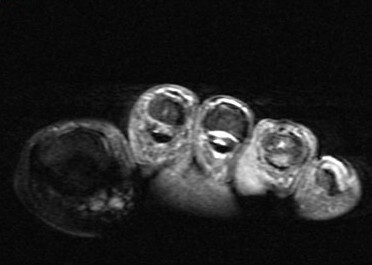

75 y/o male with toe mass.

Proven. Non painful. Mass of the skin at the base of the fourth toe. Patient sought medical attention due to the presence of the mass rather than symptoms. Last hidden image is enhanced. The disorder is rare. Reference article.

Nodular Localized Cutaneous Amyloidosis